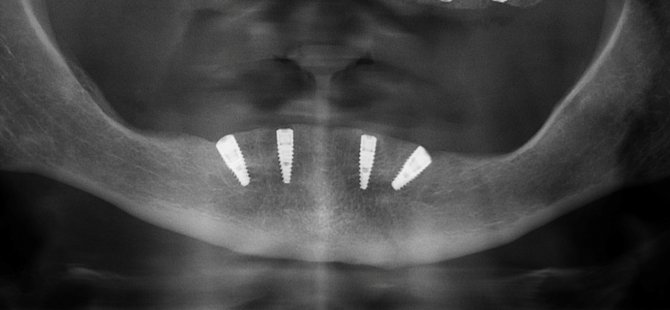

All-On-4 konseptini “toplam tedavi masrafları göz önünde tutulduğunda nispeten daha az maliyetle gerçekleştirilebilen hızlandırılmış bir tedavi yöntemi” olarak tanımlayan Doç. Dr. Özge Doğanay, “All-On-4, ileri derecede kemik erimesi olan dişsiz hastalarda sinüs kaldırma, kemik ekleme operasyonları gibi ileri cerrahi yöntemlere olan ihtiyacı azaltarak 2 adet düz, 2 adet açılı implantın yerleştirilip, uygun koşullarda aynı gün protezlerin takılabildiği bir yöntemdir. Bu uygulamada, açılı implantların yerleştirilmesi ile önemli anatomik yapılara zarar vermeden mevcut kemik en iyi şekilde kullanılarak uzun dönemli başarı elde edilebiliyor. Açılı yerleştirilen implantlar sayesinde daha az sayıda implant kullanılarak 12 adet diş yapılabiliyor. Ayrıca, bu konsept ile hemen yükleme kriterlerine sahip hastalarda cerrahiyi takiben geçici protezler hazırlanarak hasta dişli bir şekilde taburcu edilebiliyor” dedi.

Başarılı sonuçlar elde etmek için olgunun etraflıca analizi, hasta seçimi, uygun protetik ve cerrahi planlama, ekipman tedariki ve deneyimin gerekli olduğunu belirten Doç. Dr. Özge Doğanay, “Klinik ve radyografik muayene sonrasında çenelerin ve dudağın konumu, gülme hattı, anatomik yapılarla olan ilişki, kemik hacmi ve yüksekliği değerlendirilerek detaylı incelemeler yapılıyor. Ayrıca, üç boyutlu tomografilerde protez konumuna uygun olan implant açı ve pozisyonları sanal ortamda belirlenerek bu planlama rehber plaklar ile cerrahi sahaya taşınabiliyor. Rehber plaklar ile ‘All-On-4’ konseptinde operasyon süresi kısalıyor ve hedeflenen protetik planlamaya göre implantın kemik içindeki doğru pozisyonuna yerleştirilmesi sağlanıyor. All-On-4 tedavi konsepti üzerine çok sayıda araştırma var. Bu yöntemle yüksek başarı oranları elde edilmiş ve bu teknik rutin klinik pratiğine taşınmış durumda. İleri cerrahi tekniklere alternatif olarak geliştirilen bu yöntem; cerrahi ile eş zamanlı olarak protez yapılabilmesi, hasta konforunun ve memnuniyetinin yüksek olması ve nispeten daha düşük maliyetli bir tedavi seçeneği sunması ile kemik kaybı görülen çenelerin rehabilitasyonunda alternatif tedavi planlamaları arasında yerini aldı” diye konuştu.